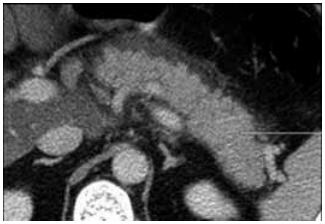

22.300/mm3; amilase: 1.040 U/L; lipase: 1.350 U/L; creatinina: 2,2 mg/dL (prévia: 0,9 mg/dL); lactato: 3,8 mmol/L;

PCR: 42 mg/dL; triglicerídeos: 210 mg/dL; AST/ALT: discretamente elevadas; pH: 7,28; HCO3–: 18; PaO2: 62 mmHg;

FiO2: 0,4. TC de abdome com contraste mostrado a seguir: